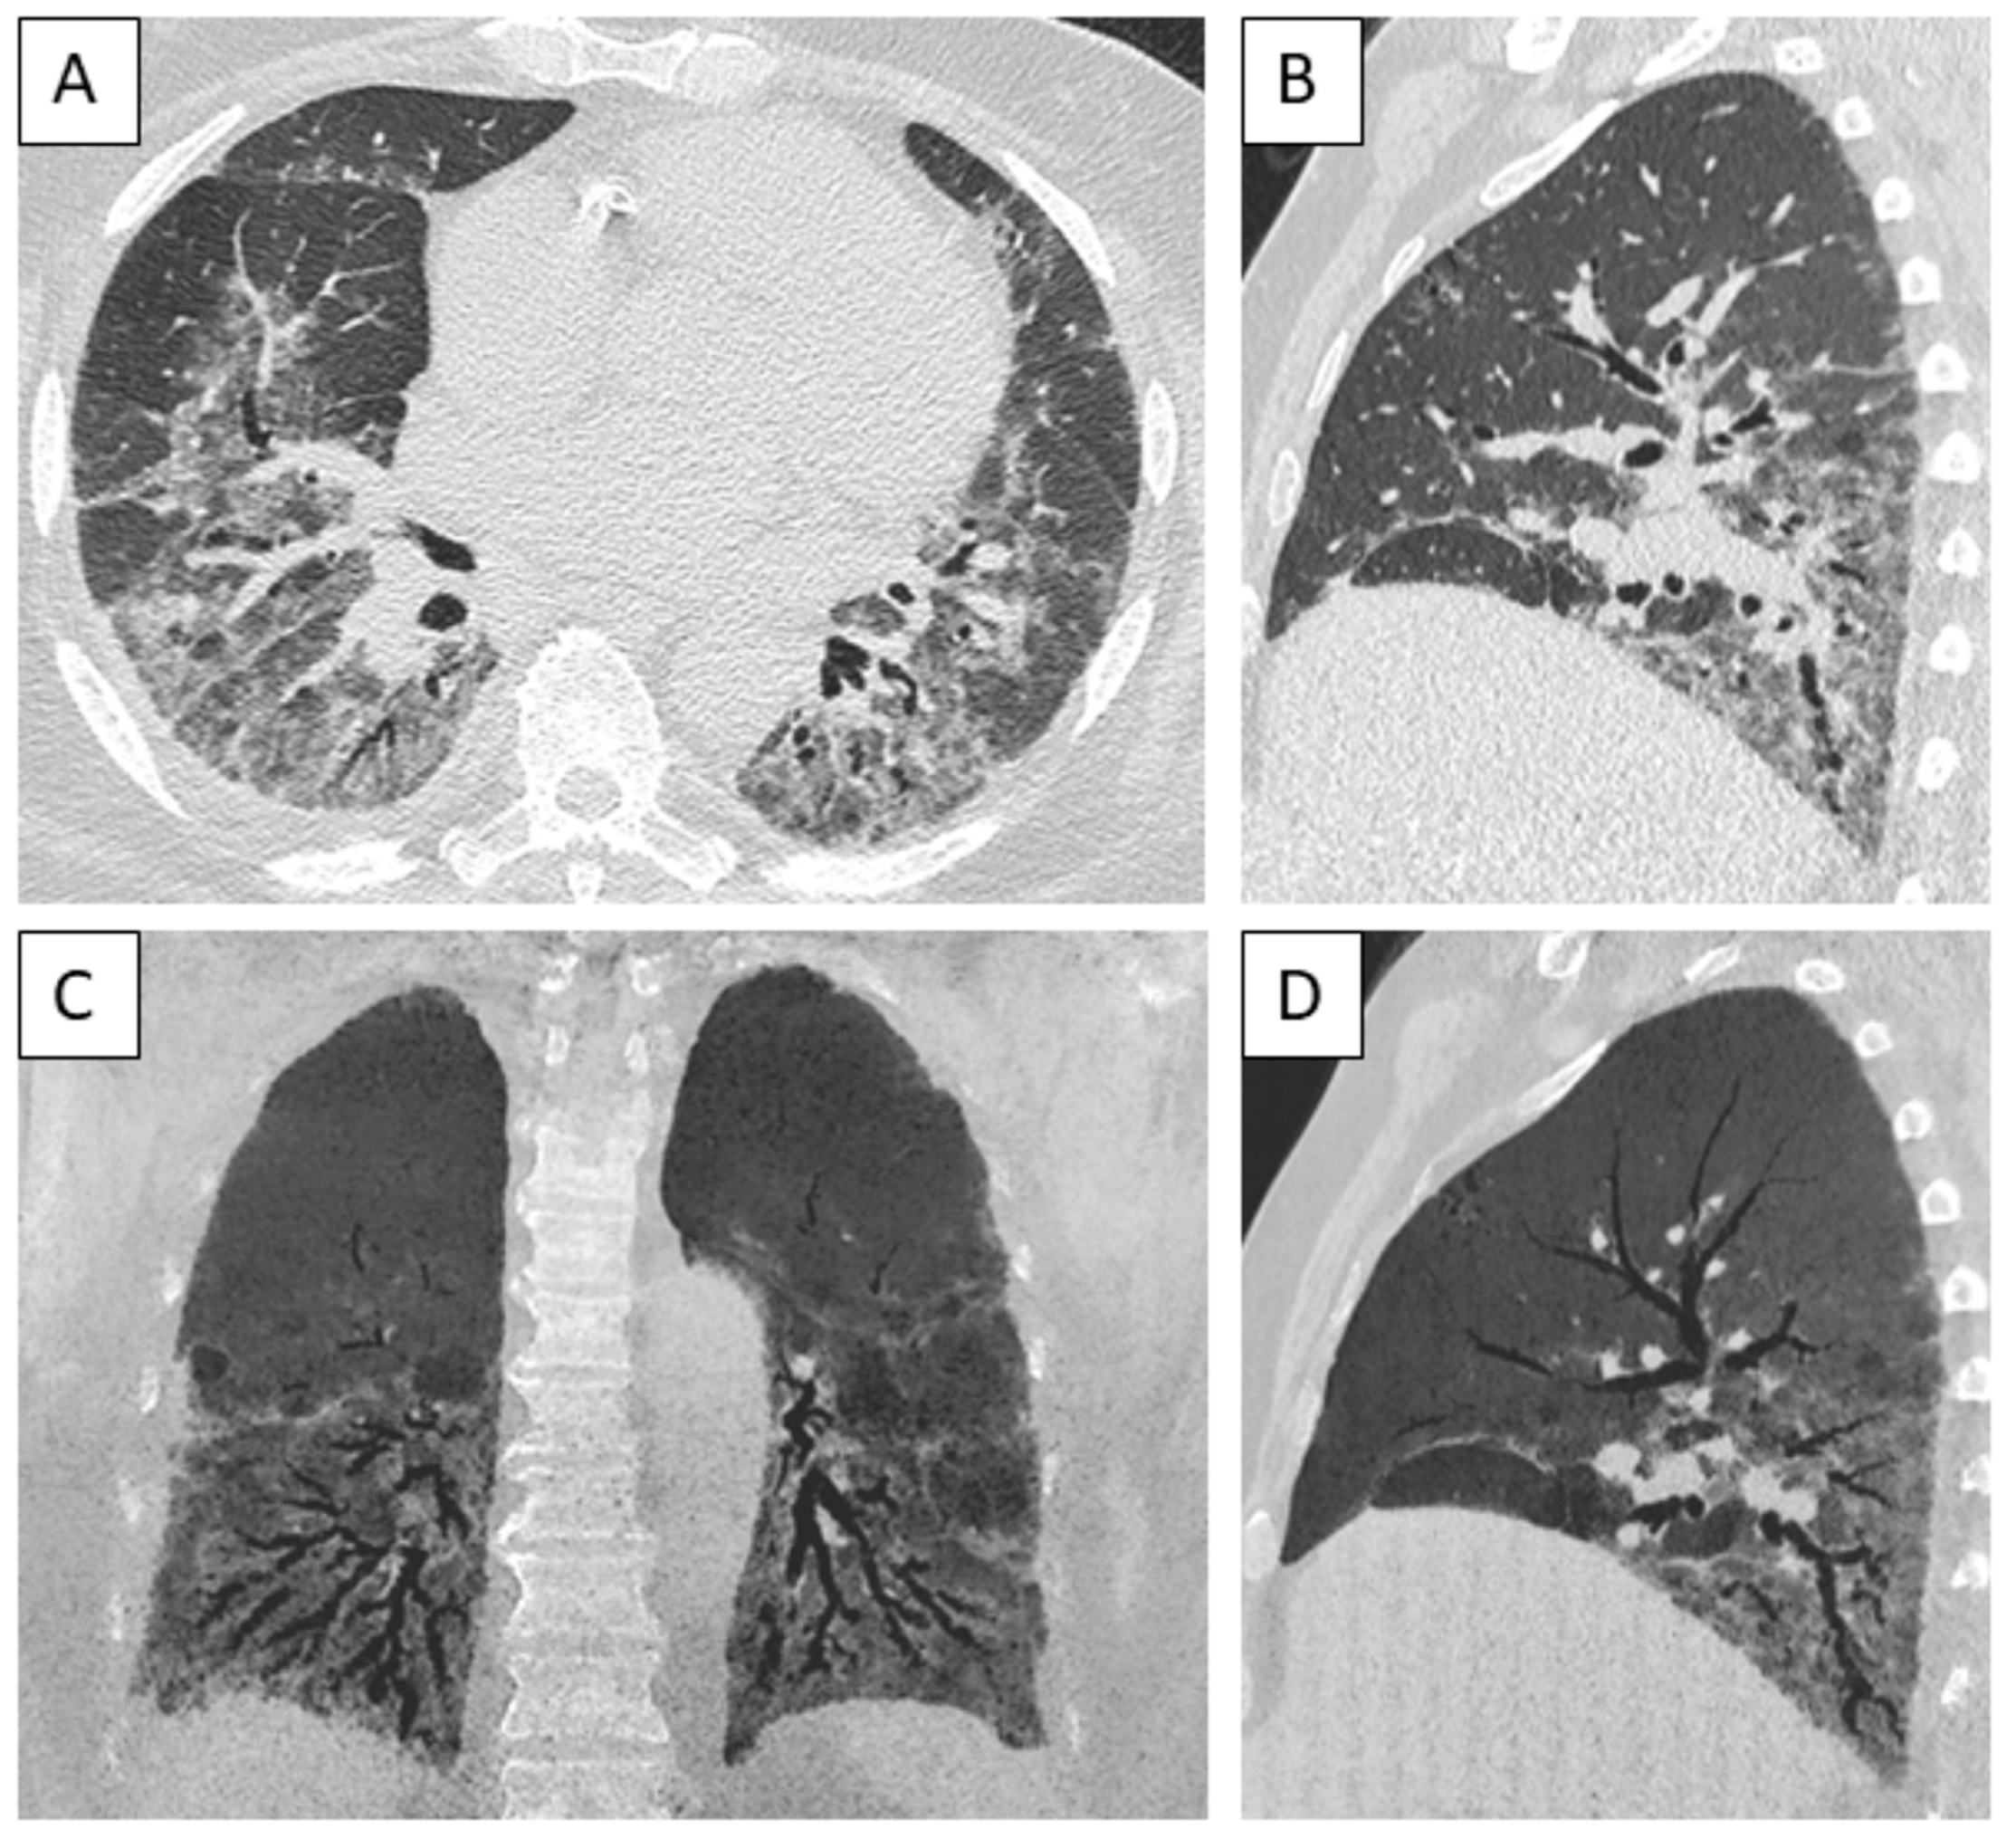

3.6. Imaging Findings

3.7. Bronchoalveolar Lavage